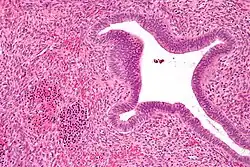

Over time the variant has been shown more commonly in people of African and of Asian descent. The clinical presentations of the gene mutation are regarded as either Microcytic or Hypochromic if they are detectable at all.[5] While the trait is not known to be abnormal on its own, the mutation of the gene can have an effect on the absorption of alcohol.[6] As well as physical difficulties with alcohol and other blood-altering substances, the hemoglobin has also been shown to effect the way the brain handles sleep disorders, like insomnia.[6] People with the G mutation are typically more likely to have issues oxygenating blood and because of this, Anemia was thought to be a side-effect of the mutation.[7]

The overall consensus among clinicians is that the "G-Philadelphia" mutation is harmless and has no clinical consequences.[8]